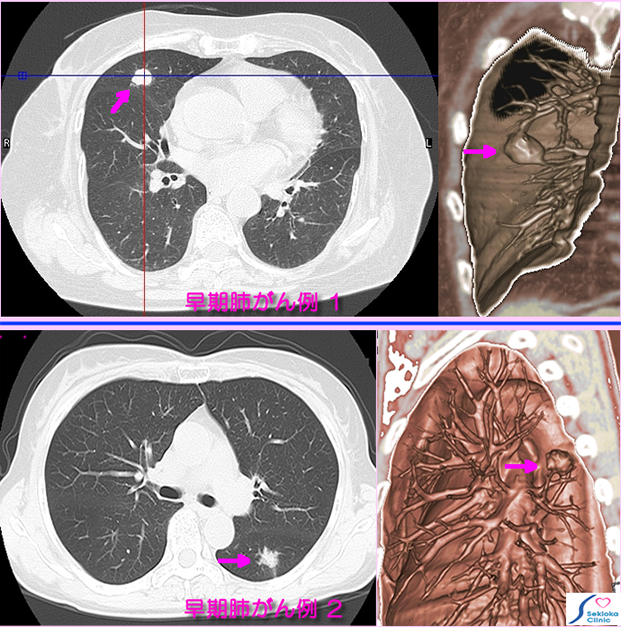

| 診断 | 添付画像の早期肺がん例1は偶然CT検査で小陰影認め(矢印)、肺がんと断定できなかったが 疑いのもとで経過観察し、4ヶ月後のCT再検査で 少し増大と陰影周辺の不規則な形状認め、肺がんの疑い濃厚となり手術。右側はMDCTによる3次元画像。下段の早期肺がん例2も 健診目的の検査で偶然見つかり、CT画像で腫瘍(矢印)の辺縁形状から腺癌が疑われ、造影MDCT検査、PET-CTの追加検査を行い手術された例。 |

| 治療 | いずれの2例も手術にて、肺門リンパ節など転移なく 早期がん。 低分化腺がん。術後の放射線照射、抗がん剤は早期がんのため使用されていない。 |